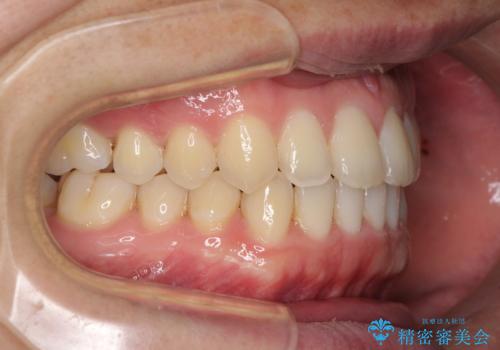

すきっ歯の改善 インビザライン矯正治療

- 上の前歯の隙間を気にして来院された患者様です。

インビザラインにより、上下の歯列を側方に拡大しつつ、前歯の隙間を閉じていくこととしました。

1日22時間の装着時間をしっかりと守ってくださったので、隙間がきれいに閉じ、口元の突出感も改善することができました。